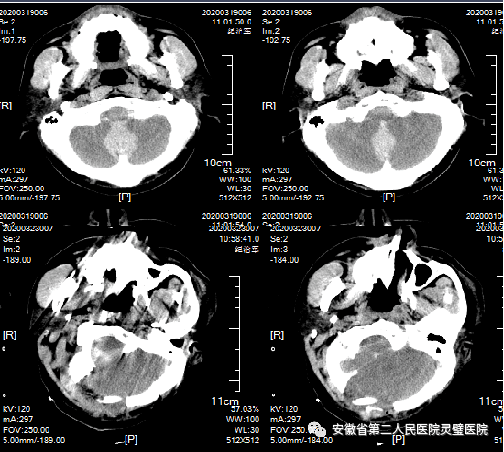

四、脑出血的综合治疗技术

脑出血是临床常见神经重症,原发性高血压是最常见原因之一,根据病人的不同特点,我科形成了从保守治疗、微创治疗到去大骨瓣减压等系列个性化特色技术,临床救治水平达到国内先进水平。

经额穿刺血肿引流术

经颞小骨窗神经内镜下血肿清除术

去大骨瓣减压术+脑内血肿清除术